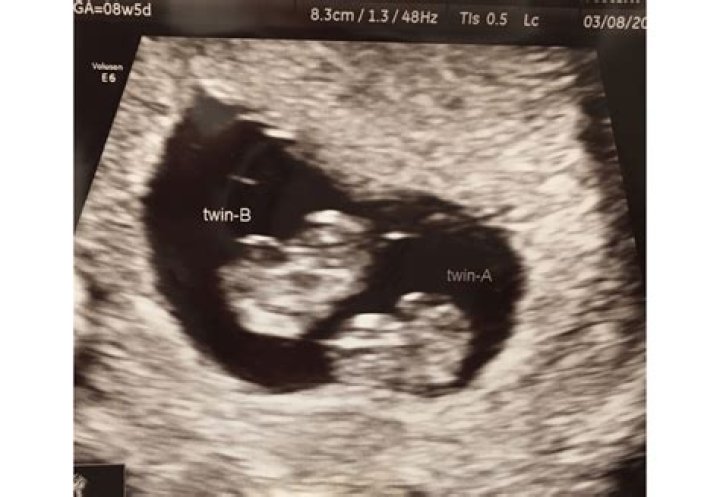

Can you tell if you are having twins at 8 weeks?

Ultrasound. Although the factors above may be signs of a twin pregnancy, the only sure way to know you're pregnant with more than one baby is through an ultrasound. Some doctors schedule an early ultrasound, around 6 to 10 weeks, to confirm the pregnancy or check for issues.

Can you miss a twin at 8 week ultrasound?

The baby's heartbeat can't usually be detected before about 7-8 weeks, but some scans are performed before this. If one of the tiny twins happens to be hidden behind the other when the scan is performed, then there might not be any clue that you're carrying more than one baby.